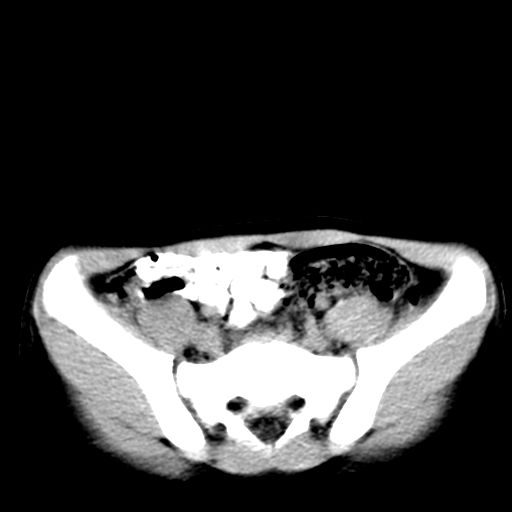

腹部好象未见异常。

腹部ct平扫未见明确异常

腹部ct平扫不能提示哪里有病变。